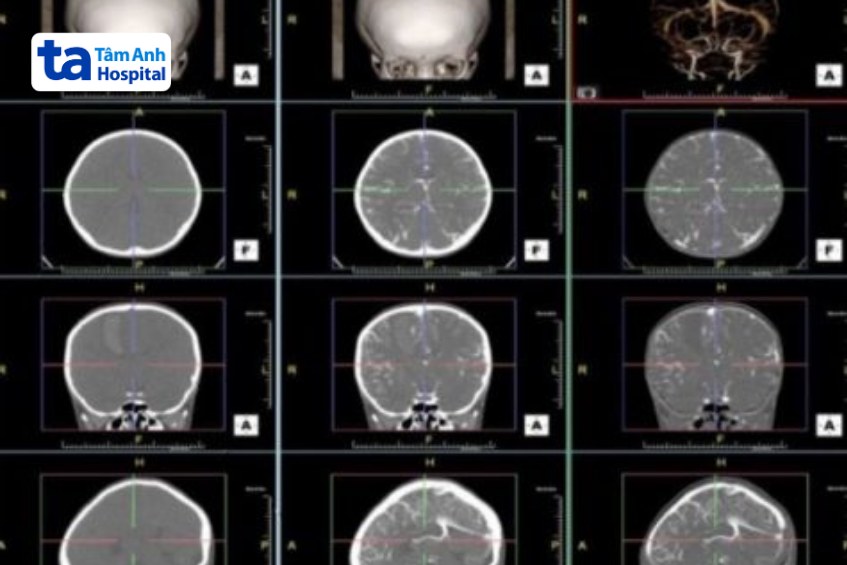

Chụp CT 16 dãy là kỹ thuật tạo nên hình ảnh giải phẫu các cơ quan trong cơ thể, bằng cách sử dụng tia bức xạ X được phát ra từ máy chụp cắt lớp điện toán với 16 đầu dò.

Chụp vi tính cắt lớp 16 dãy sọ não hỗ trợ chẩn đoán: